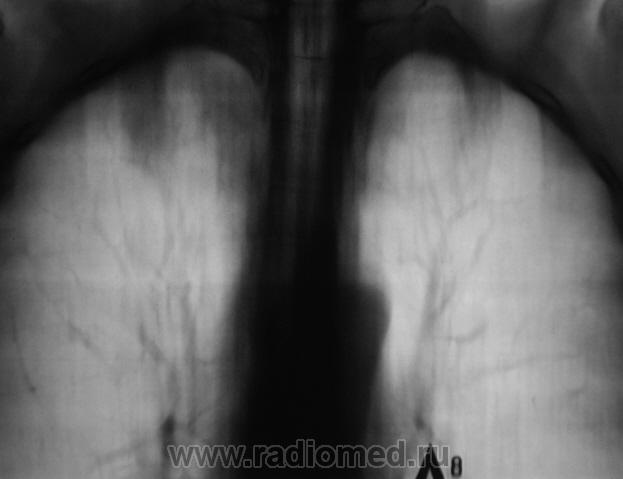

Пол пациента: Мужской пол Тип патологии: Инфекция Область исследования: Грудная клетка и верхние дыхательные пути Методы исследования: Rg При расшифровке цифровых флюорограмм пациент "взят на контроль". Смутила правая верхушка. Произведено стандартное дообследование. Ваше мнение коллеги? Пнд, 19/10/2009 - 22:26 #1 Наталия Не на сайте Был на сайте: 8 лет 7 месяцев назад Зарегистрирован: 30.07.2008 - 13:24 Публикации: 538 Полость на правой верхушке. Втр, 20/10/2009 - 07:40 #2 OPEXOB Не на сайте Был на сайте: 9 лет 11 месяцев назад Зарегистрирован: 26.07.2008 - 10:02 Публикации: 280 Ничего особенного. Повышенная пневмотизация и только. А томография 1 ребра хорошая. Втр, 20/10/2009 - 19:52 #3 Катенёв Валенти... Не на сайте Был на сайте: 7 лет 2 недели назад Зарегистрирован: 22.03.2008 - 22:15 Публикации: 54876 А что по поводу "полостного образования" мкажите коллега? Втр, 20/10/2009 - 20:08 #4 serega Не на сайте Был на сайте: 12 лет 4 месяцев назад Зарегистрирован: 15.10.2009 - 18:10 Публикации: 99 Прилежащая легочная ткань интактна- признаков воспаления нет, стенки плотные, полость "пуста". Быть может процесс старенький? Втр, 20/10/2009 - 20:17 #5 Глазков Игорь А... Не на сайте Был на сайте: 9 месяцев 2 недели назад Зарегистрирован: 19.12.2008 - 20:41 Публикации: 1597 похожа на туберкулёзную каверну. Прийди к Себе

Полость на правой верхушке.

Ничего особенного. Повышенная пневмотизация и только. А томография 1 ребра хорошая.

Прилежащая легочная ткань интактна- признаков воспаления нет, стенки плотные, полость "пуста". Быть может процесс старенький?

похожа на туберкулёзную каверну.